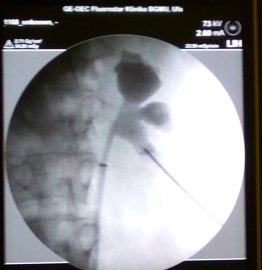

Within the framework of the event, for the first time in the Republic of Bashkortostan, two operations were carried out – microcutaneous nephrolithotripsy. The operations were performed by Andrey Andronov, Ph. D., assistant of the Urology department of “Institute of advanced training of Russian FMBA", the Urology and Andrology department of State Research Center Burnazyan Federal Medical Biophysical Center of Federal Medical Biological Agency, Moscow.

A distinctive feature of this operation is the fact that the stone is removed through a puncture in the lumbar region with a maximum diameter of up to 3.5 millimeters. The advantages of this technology are the absence of cosmetic defects, a short period of hospitalization, rapid recovery of working capacity for patients.